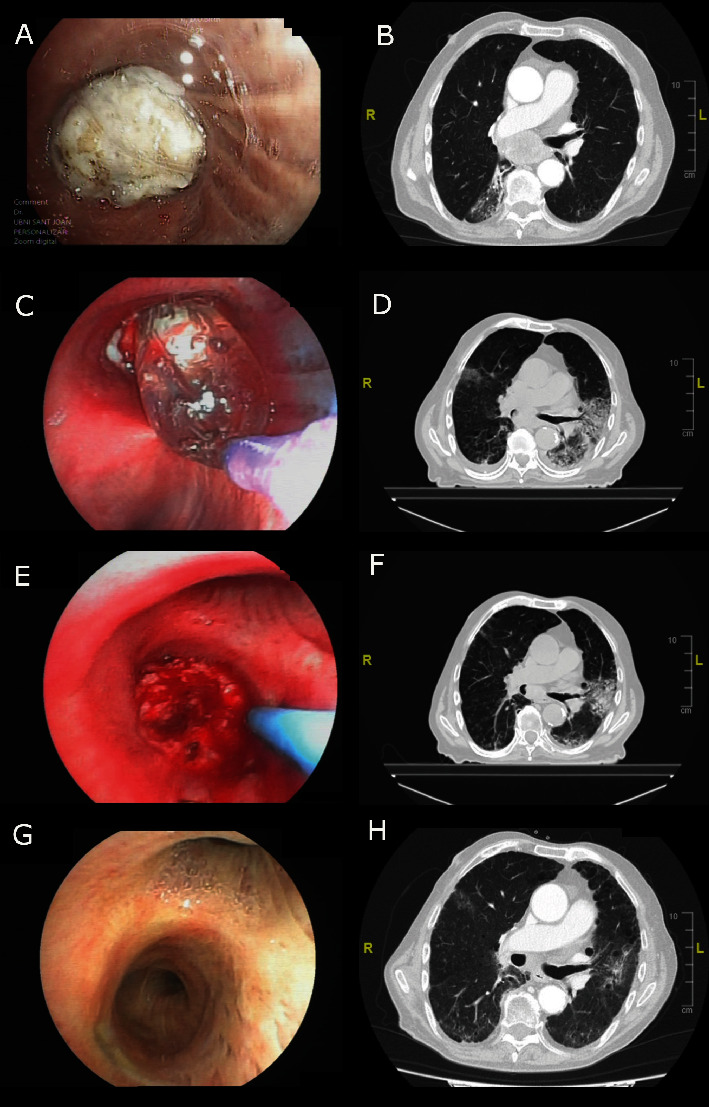

介入性肺病学对恶性气道狭窄病例很有帮助。我们为大家介绍一位被诊断为肺癌的 73 岁男性患者,他因支气管内巨大肿瘤而出现无症状的气道狭窄。患者接受了化疗、放疗和多模式支气管镜治疗,包括气囊支气管成形术、电外科手术和氩等离子凝固术。疗效评估显示,患者症状缓解,支气管内肿瘤消失,气道狭窄完全消除。

Interventional pulmonology can be helpful in cases of malignant airway stenosis. We present a 73-year-old man diagnosed with lung cancer who presented with symptomatic airway stenosis caused by a large endobronchial tumor. Oncological treatment was started with chemotherapy, radiotherapy, and a multimodality bronchoscopic approach using balloon bronchoplasty, electrosurgery, and argon plasma coagulation. Response evaluation showed relief of symptoms, disappearance of the endobronchial tumor, and complete resolution of the airway stenosis.